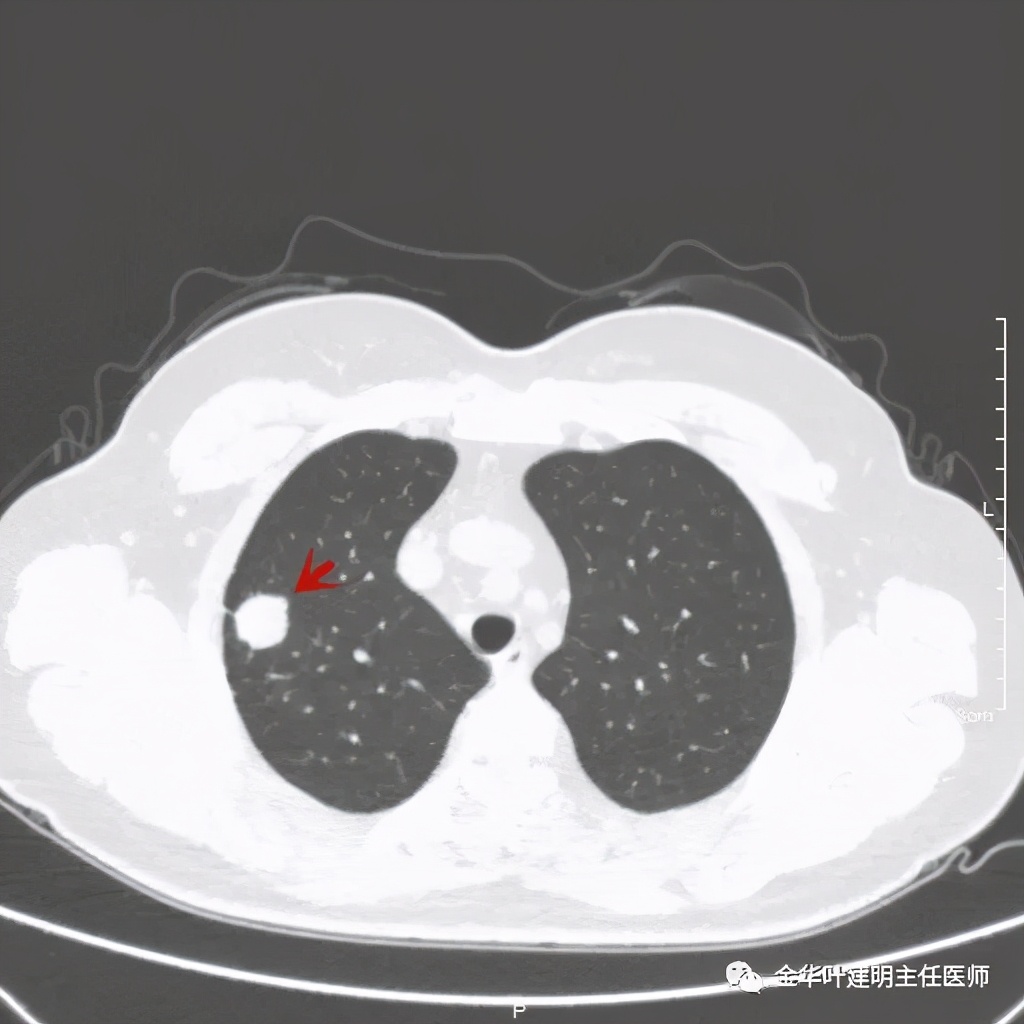

主病灶非常光滑

上图同样示与胸膜近,但无牵拉

上图示病灶内侧有个小的空泡